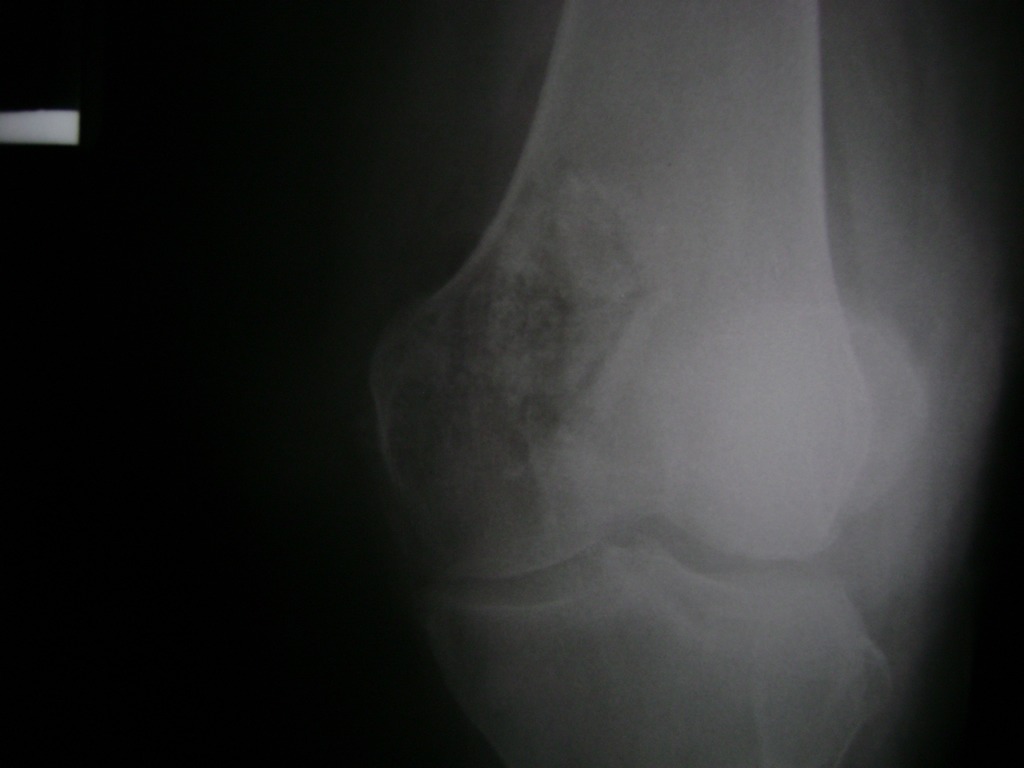

Cirugías de Peroné y Tibia

La artroscopia de rodilla es un cirugía en el cual la estructura interna de la articulación es examinada ya sea para realizar un diagnostico o para realizar un tratamiento, este procedimiento se realiza utilizando un instrumento parecido a un pequeño tubo llamado artroscopio.